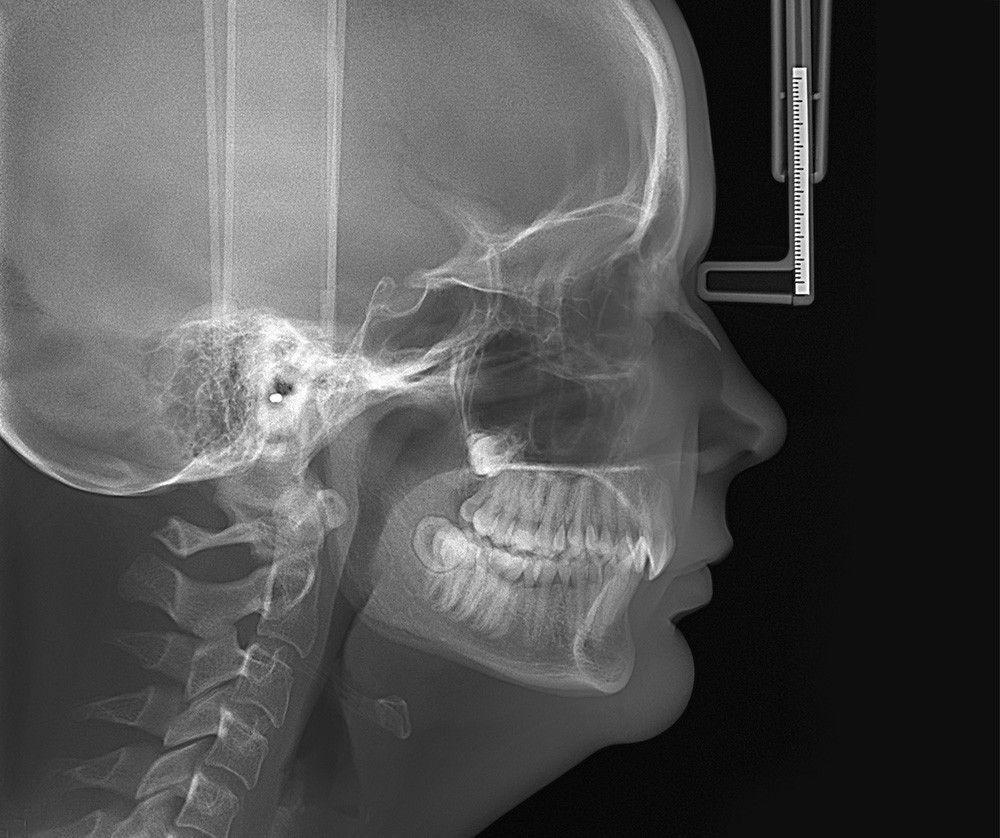

Желаемая область съёмки выбрать интуитивно, при помощи стоматологической карты ORTHOselect. Пользователь может выбрать зубы индивидуально или верхнюю и нижнюю челюсть целиком, или ВНЧС, необходимый размер области сканирования установится автоматически на основе произведённого выбора.